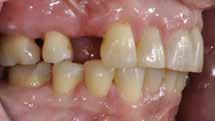

Den kliniske undersøgelse viser harmoniske ekstraorale sagittale forhold med skeletalt dybt bid (Fig. 1A, D). Hendes smil er alderssvarende med en eksponering på 8/10 af overkæbeincisiverne, mens smilets bredde er smalt med synlige mørke laterale rum (Fig. 1D). Underkæbeincisiverne er synlige under tale. Der ses neutrale okklusale forhold ved hjørnetænderne og neutrale pladsforhold i overkæben, men udtalt trangstilling i underkæben især lokaliseret i regio 1-1 (Fig. 1C).

Sliddet klassificeres som grad 2 (moderat tandslid) på de centrale incisiver i overkæbe og underkæbe. Det kan anses som patologisk, da det er atypisk for patientens alder, giver anledning til smerte/ubehag, og giver patienten et æstetisk problem. Der ses infraktioner af overkæbeincisiverne. Der ses endvidere en udtalt Spee-kurve i underkæben og ingen interincisal afstøtning på 2-2 med let ganepåbidning.

Røntgenanalyse viser fravær af -6 samt et velholdt tandsæt uden tegn på sygdom. Profilrøntgenbilledet viser et skeletalt

dybt bid, men normal inklination af fortænder i over- og underkæbe (Fig. 1B).

Behandlingsovervejelser og -plan er, at en behandling med fast apparatur med høj effektivitet vil kunne adressere de vertikale forhold med fokus på nivellering af Spee-kurven i underkæben via intrusion af underkæbeincisiverne og relativ proklination. Den sagittale ekspansion vil skabe plads, og interproksimal reduktion (IPR) af incisiverne kan overvejes.

Ved behandlingssamtalen udtrykker patienten imidlertid et klart ønske om en mere kosmetisk apparaturløsning, og vi drøfter mulighed for Clear Aligner Therapy (CAT). Alignere anses af ortodontister som en mindre optimal metode til korrektion af dybt bid pga. udfordringer med nivellering af Speekurven. I dette tilfælde faciliterer trangstillingen imidlertid en proklination af underkæbeincisiverne. En ideel visualisering/ simulationsplan udarbejdes i softwareprogrammet (Fig. 2A). Her anvendes ortodontiske principper kendt fra CAT, såsom sekventiel intrusion af underkæbeincisiver og hjørnetænder i stadier, overkorrektion af ekstrusionen af underkæbepræmolarerne, distal kipning af underkæbemolarerne, samt placering af

horisontale attachments på præmolarerne for

at understøtte nivelleringen (Fig. 2B-D). En mindre korrektion af det gingivale niveau i overkæbe samt distorotation og mindre distalisering af overkæbemolarerne planlægges.

I samråd med patienten og egen tandlæge* afstemmes forventningerne, inden der bestilles refinement alignere. Nivelleringen af alle tænder i tandbuerne, smilelinje og -kurve samt den bukko-lingvale position af incisiverne foretages og efterfølges af retainers lingvalt på over- og underkæbeincisiver (Fig. 3 A-D). Hele behandlingen udføres under løbende kommunikation med patient og egen tandlæge*, der udfører den efterfølgende rekonstruktion med direkte plast (Fig. 4 A-D). Behandlingsvarigheden har været to år og to måneder, hvor ortodontien har forløbet over 21 måneder. Der har været anvendt et første sæt på 66 alignere samt yderligere to sæt med ni refinement alignere. Tandblegning og direkte plastrekonstruktion er udført af egen tandlæge* (Fig. 5 A-F).